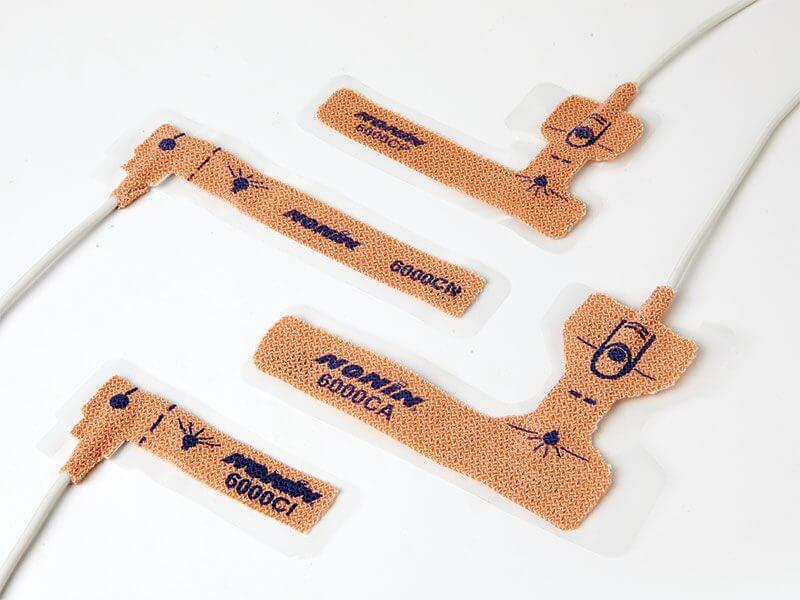

Nemi fyrir súrefnismettun – einnota fullorðins

- Available in a Variety of Sizes With sizes from neonate to adult you can ensure a proper fit for a reliable reading